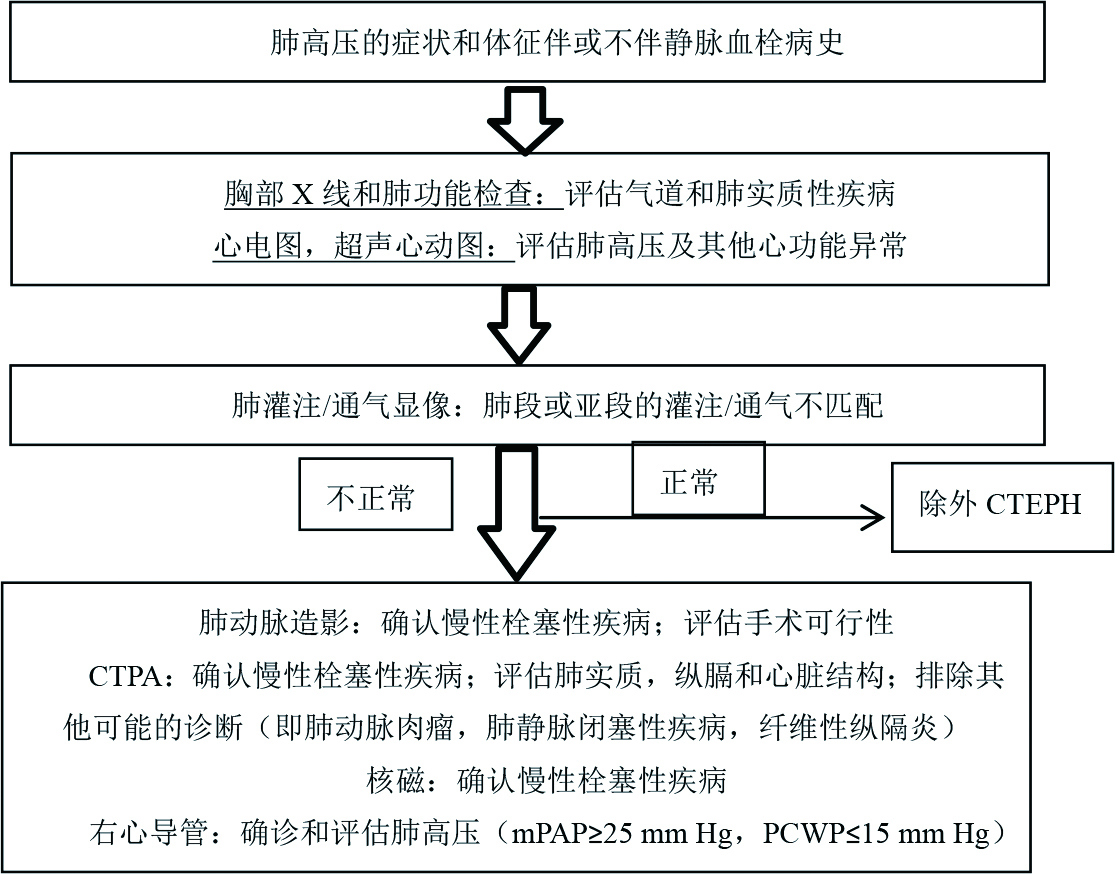

4.2 诊断时机及手段急性肺栓塞需经过正规抗凝治疗3月后,如右心导管仍存在mPAP≥25 mmHg,PAWP≤15 mmHg方可诊断。CTEPH仅依靠病史及体格检查诊断非常困难,更常见的心肺疾病如心肌病,缺血性心脏病,限制性或阻塞性肺疾病均可有相似的症状或体征[13]。胸片及肺功能有助于除外气道疾病及肺实质性疾病、心电图可发现肺高压与其他心脏疾病的蛛丝马迹、超声心动可用于筛查怀疑有肺血管疾病的患者是否存在肺动脉高压及右心功能不全、肺灌注/通气是筛查CTEPH的重要手段,其敏感性为96%~97.4%[13, 37]。诊断CTEPH的影像学金标准为肺动脉造影,肺动脉增强CT因分辨率高、无创等优势趋于取代肺动脉造影,但肺动脉增强CT敏感性要低于肺通气灌注显像,检测肺动脉主干的敏感性和特异性分别为97%及97.1%,而检测远端肺动脉栓塞的敏感性仅为85.8%,特异性为94.6%[38]。2018年JACC指南推荐CTEPH的诊断流程为:依据症状、体征及病史等疑似CTEPH时进行胸部X线、肺功能、心电图、超声心动检查等检查,除外其他疾病后完善肺灌注通气显像,结果正常即可除外CTEPH,如结果异常,则需进一步完善CTPA、右心导管等有创检查进一步明确诊断[18](表 2,流程图见图 2)。